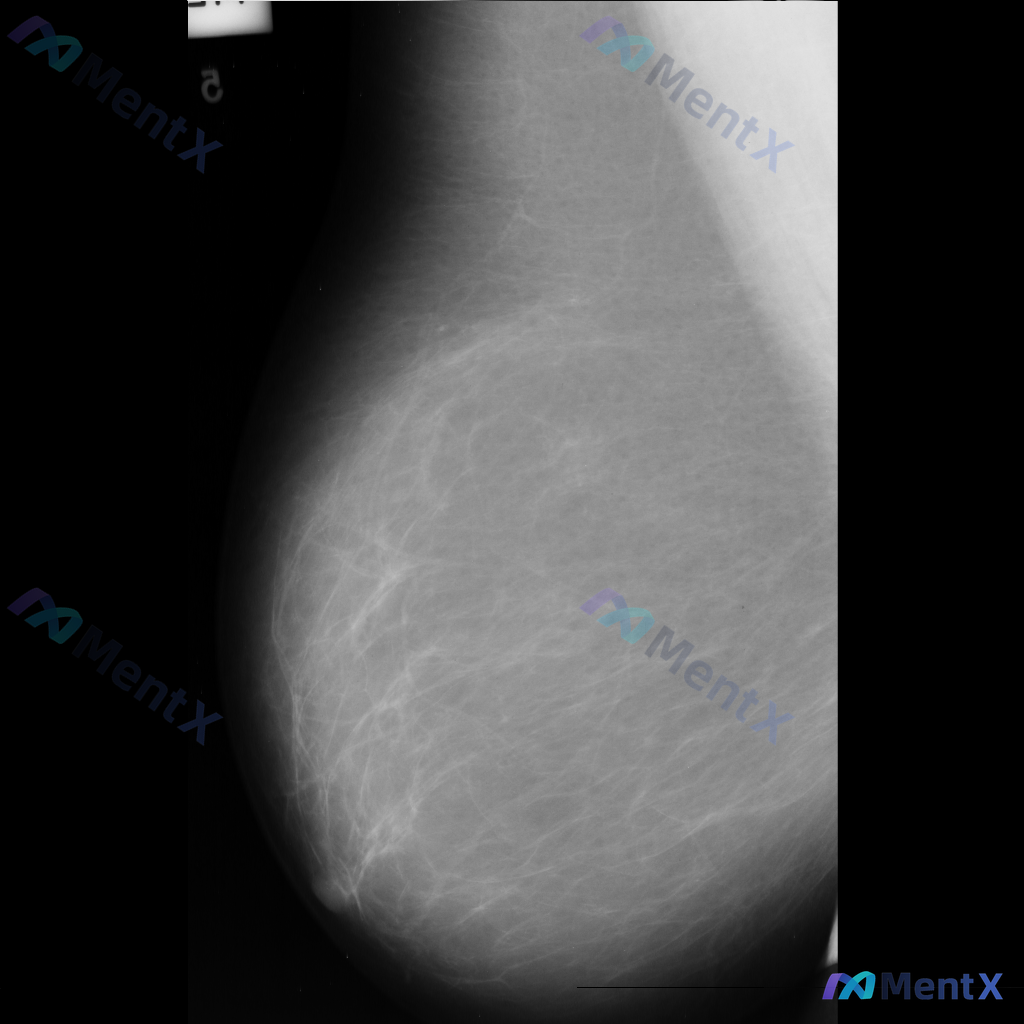

整理到一份单张的乳腺钼靶影像资料,仅有单侧、单幅图像,没有对侧对照,也不确定是MLO位还是CC位。 目前能看到的信息大概是: - 乳腺类型看起来是多量腺体型 - 图像上没有看到明确的肿块、可疑的恶性钙化 - 皮肤、乳头、血管这些能看到的部分没有明显异常(不过图像范围没包含腋窝) 这种情况下,大家觉得...

整理到一张左乳内外斜位(MLO)的钼靶影像资料,先和大家讨论一下读片的情况。 目前已知的信息: - 仅提供了左乳的MLO位单张投照影像 - 影像质量基本良好,基本结构可辨 - 后续补充说明提到患者的乳腺构成类型为不均匀致密型(BI-RADS C) 目前暂时没有更多临床病史、对侧乳腺影像或头足位(CC...